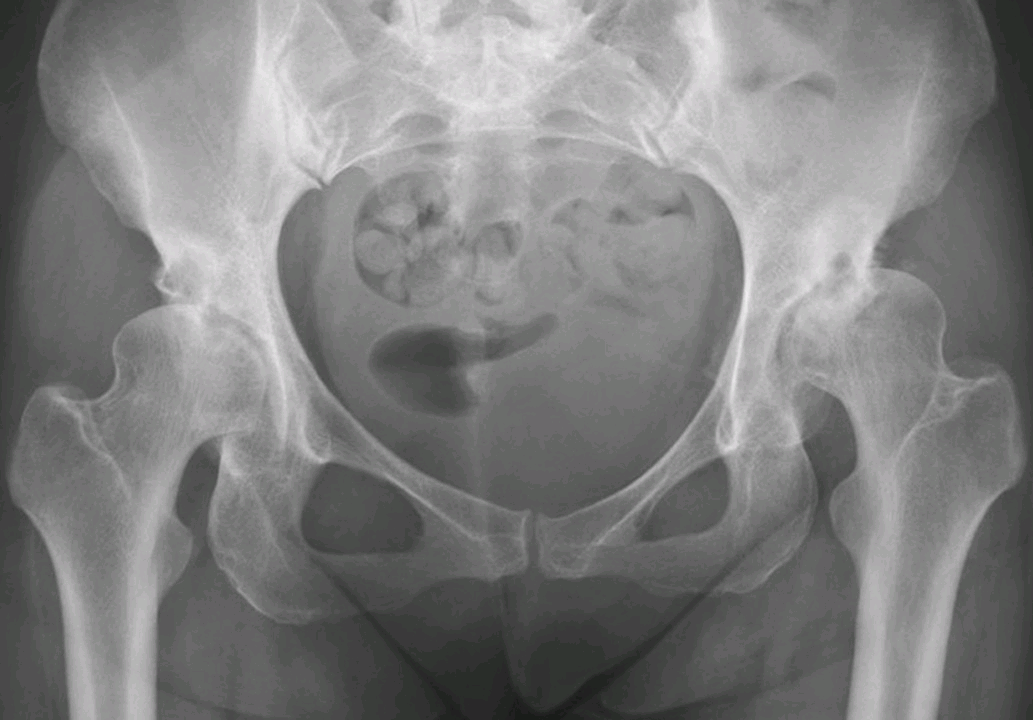

双侧髋臼发育不良伴退行性骨关节病

双髋正位片,示双侧髋臼变浅,Sharp角增大,左股骨头外上方半脱位,髋臼顶关节面下均见边缘硬化之囊变,间隙均变窄,股骨头稍变扁,股骨颈干角稍增大